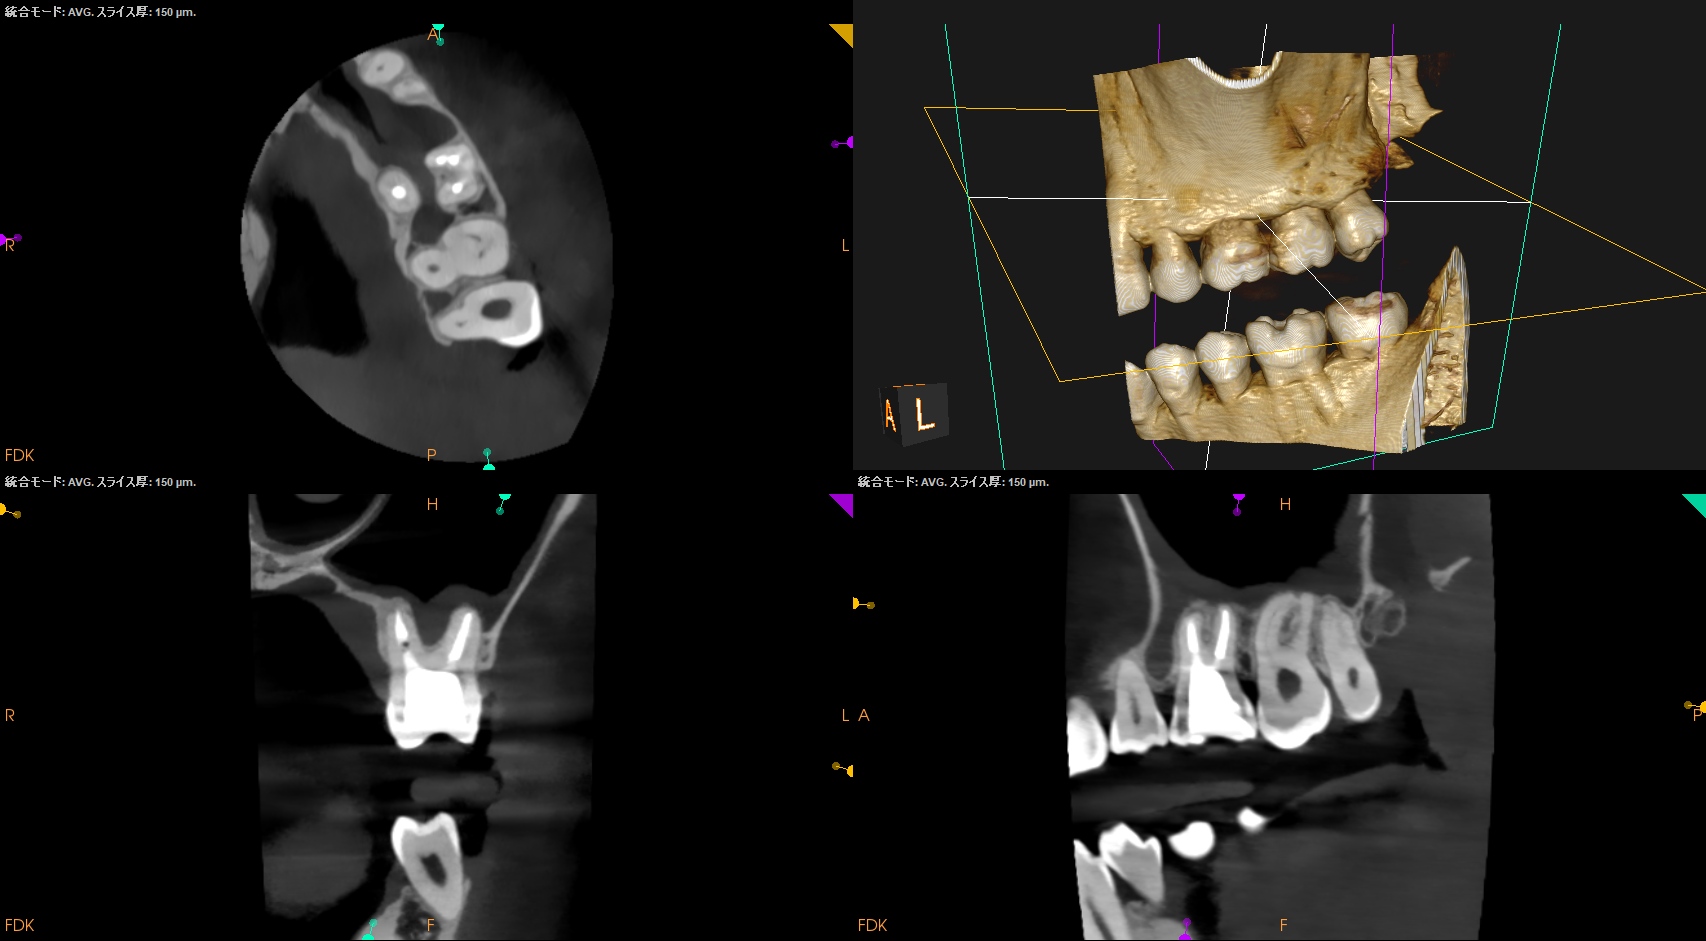

#14 Re-RCT 6yr recall(2026.1.27)

MB

MB2

DB

P

根尖病変は消失した。

また、再治療直後に根尖孔外へとはみ出たGutta Percha Pointの残渣も消失した。

CBCTがなければ術前の臨床状況を正確に判断できないのである。

やはり改めて全てのケースでCBCTを撮影するべきだと思い知らされた6yr recallであった。